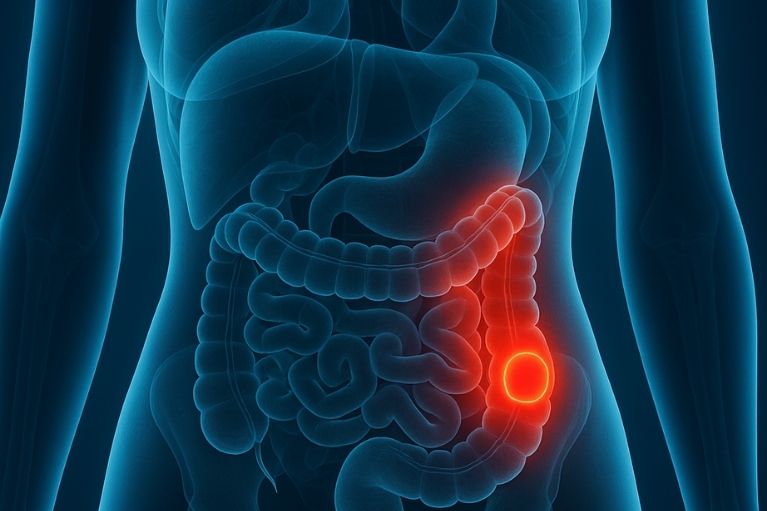

É um dos tumores malignos mais comuns e, na maioria dos casos, potencialmente curável com cirurgia quando diagnosticado precocemente. Tem ótimos resultados com cirurgia robótica.

Caracterizada pela presença de pequenas bolsas (divertículos) na parede do intestino. As possíveis complicações são sangramento, inflamação (diverticulite) e até perfuração intestinal.

Sangramento nas fezes, alteração do hábito intestinal, como diarréia ou intestino preso; cansaço e fraqueza causada por uma possível anemia, perda de peso sem causas notáveis, dor ou desconforto abdominal constante.